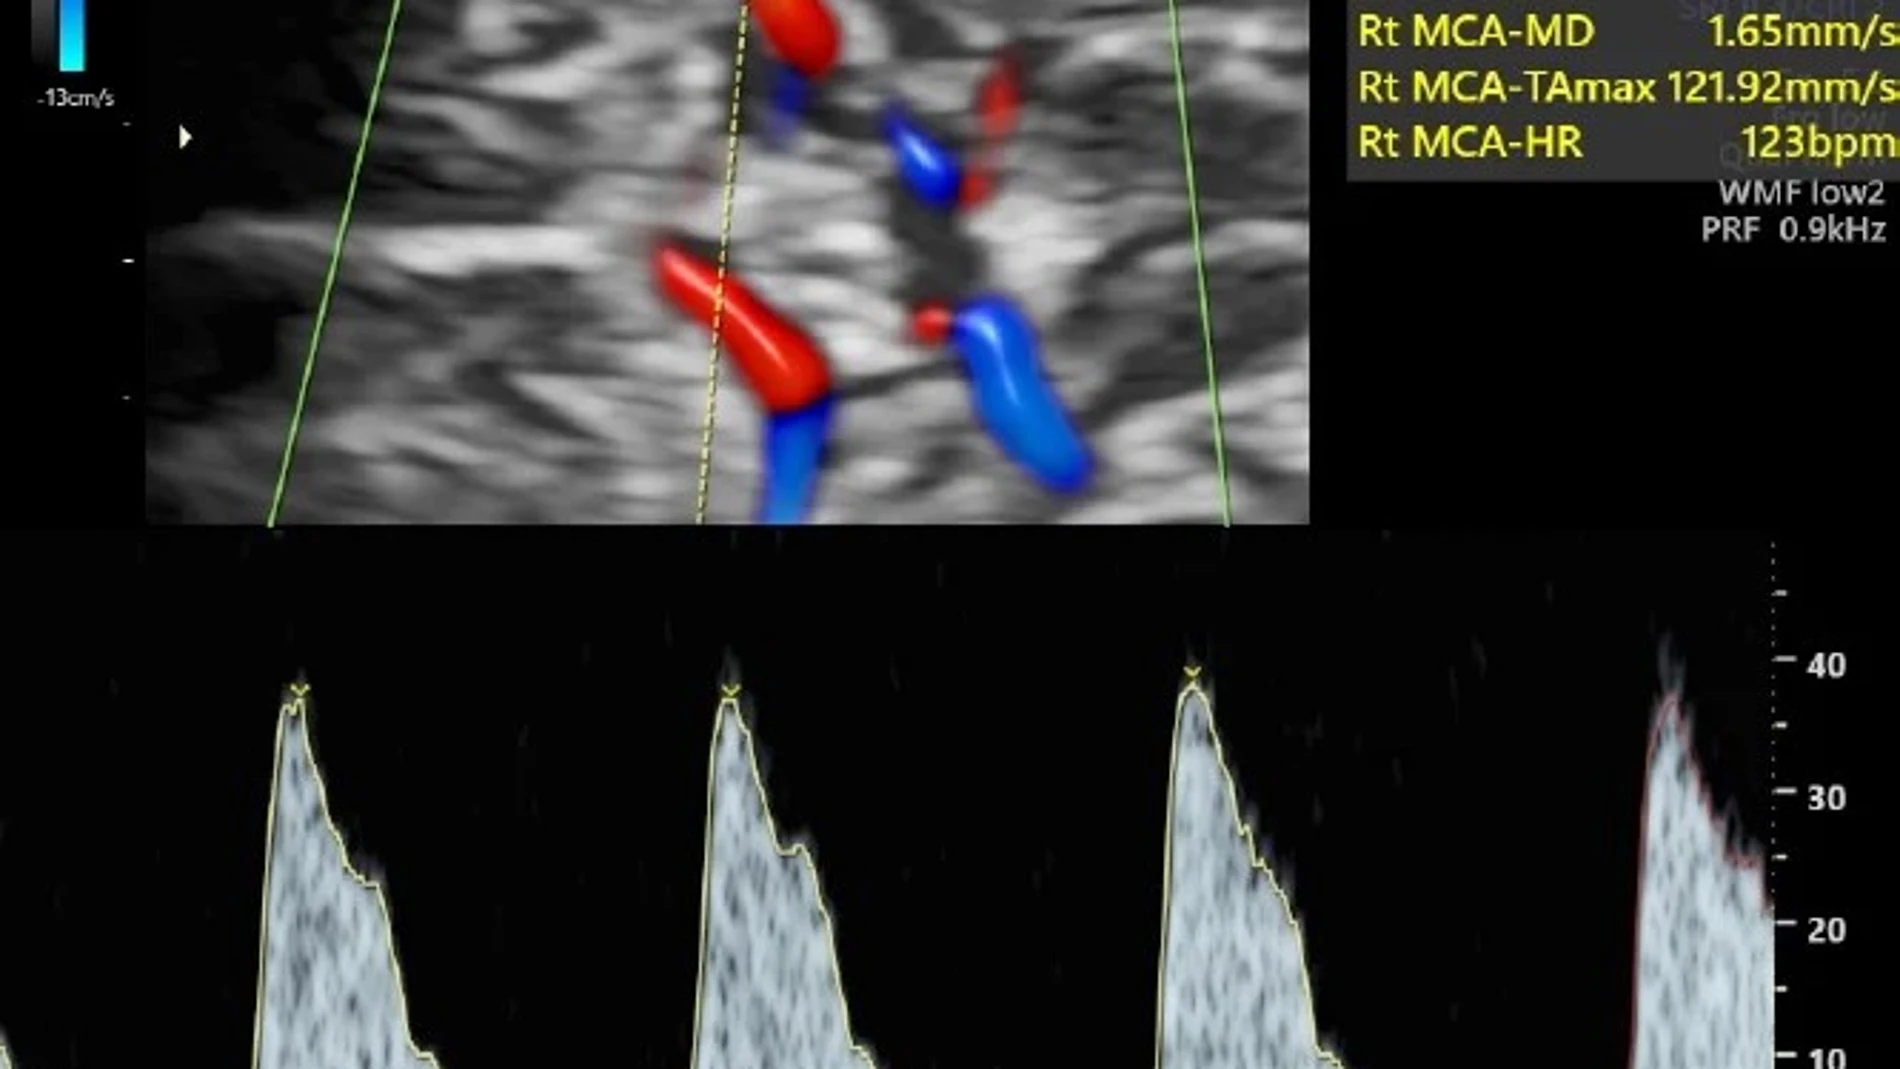

En este contexto, a día de hoy ya existe una prueba con ecografía Doppler que permite medir la circulación de la sangre por el cordón umbilical y el cerebro y que, por lo tanto, permite identificar el riesgo de insuficiencia placentaria, sin embargo ésta se lleva a cabo exclusivamente en embarazos con problemas. Solo en casos muy indicados se practica esta prueba a las gestantes, lo que hace ya más de una década abrió un debate entre los profesionales acerca de si era conveniente hacerla extensiva a todas las mujeres embarazadas o bien el gasto en recursos y la baja incidencia de la insuficiencia placentaria lo hacía innecesario.

En este contexto, se acaba de publicar en la revista The Lancet los resultados de un estudio internacional multicéntrico, concebido y dirigido por el jefe del servicio de Medicina Fetal del Hospital Clínic, Francesc Figueras, y el director de BCNatal, Eduard Gratacós, el cual ha contado con el apoyo de la Fundación “la Caixa”, que confirma que el recurrir a Doppler en la ecografía de rutina del tercer trimestre para medir el flujo de los vasos del cerebro del feto y de la placenta permite detectar los casos de riesgo de complicaciones posparto que requieran el ingreso del bebé en la UCI y el inducir el parto al término de la gestación cuando se detecte ese riesgo podría reducir a la mitad la tasa de ingreso en la UCI neonatal.

En el estudio han participado durante 6 años más de 11.500 mujeres con embarazos de bajo riesgo, a quienes se les midió la circulación de la sangre por el cordón umbilical y el cerebro del bebé mediante Doppler en la ecografía de las 36 semanas, pero solo en algunas se usó esa información para cambiar el abordaje de la gestación, de manera que no en todos los casos en los que la prueba salió alterada se planteó la inducción del parto.